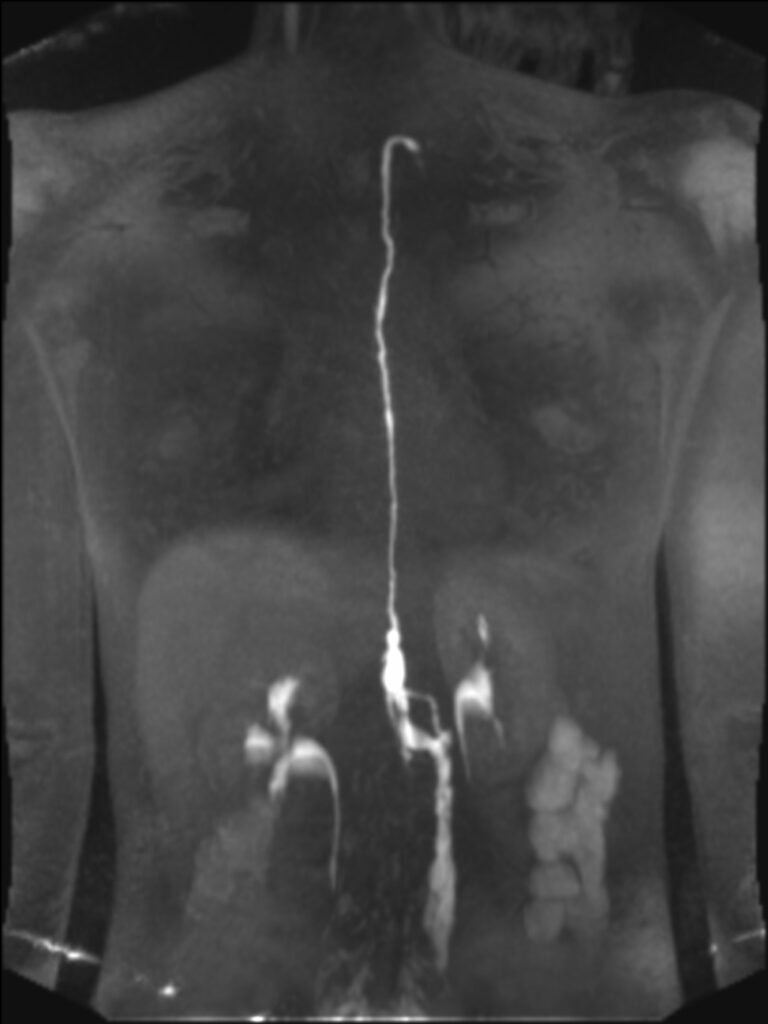

The patient is then positioned in the MR scanner and gadolinium-based contrast agent (Dotarem, Guerbet Group, Princeton, NJ) is injected into the lymph nodes.The acquisition techniques include three elements (we using Siemens equipment, however, all other manufactures have similar sequences):

02. Fast angio acquisition technique (TWIST)

- 1. Dynamic evaluation of the lymphatic flow (how fast lymph flows)

03. Delayed high resolution angio technique (Inversion recovery with fat suppression)

- 1. Allows for delayed images, when the timing of the contrast material is slower

- 2. High resolution images of the lymphatic system